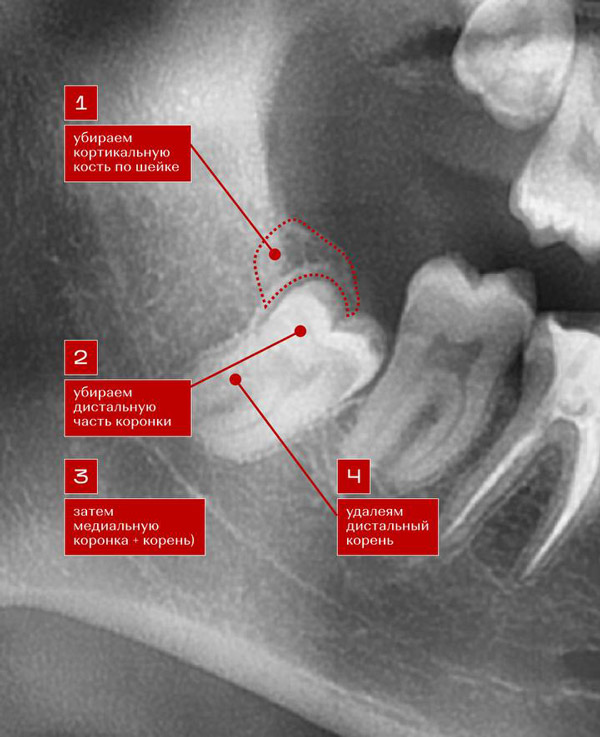

Чаще требуется разрез десны и даже удаление части кости для доступа к зубу. Иногда зуб разделяют на несколько частей для облегчения его удаления.

Требуется провести разрез десны, а в некоторых случаях – иссечь кость, если зуб «лежит» в ней.

Может потребоваться разделение зуба на части для облегчения извлечения. Сначала убирают фрагмент, который упирается в соседний зуб, а затем корни.